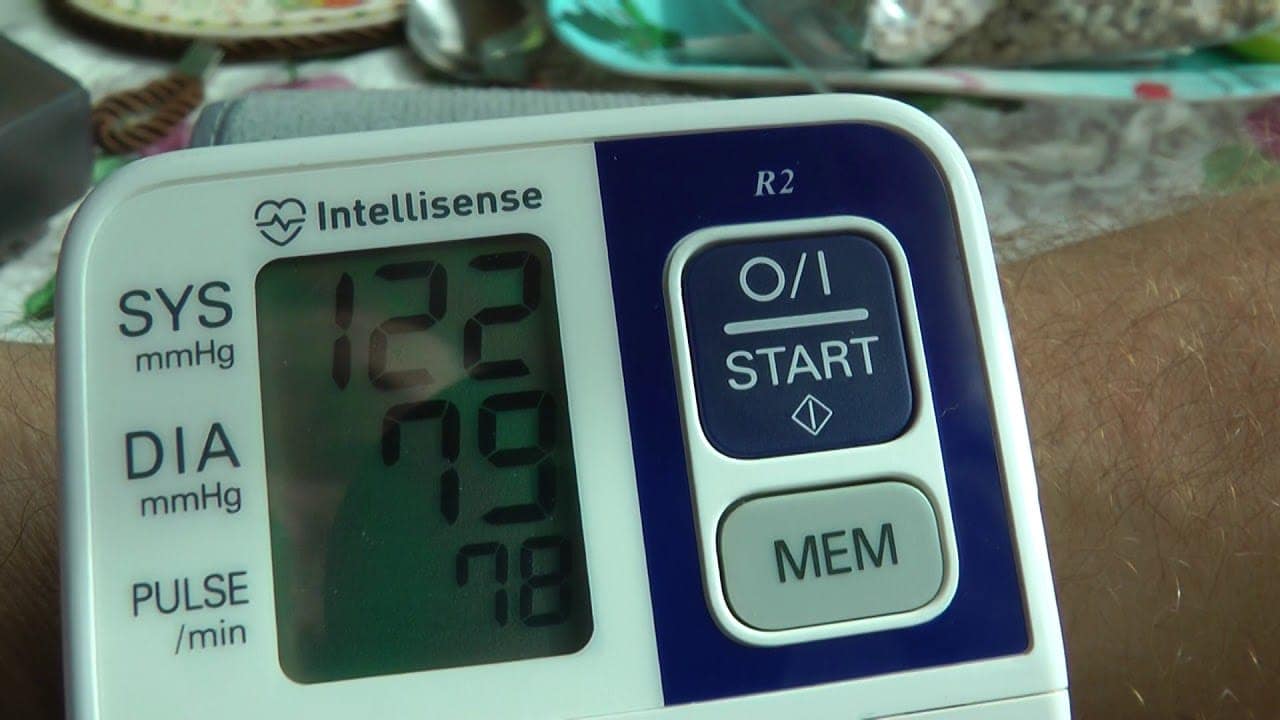

После 9-10 недель регулярного приема Cardiodoc давление не просто снижается. оно стабилизируется до возрастной нормы, и резкие перепады больше вас больше не беспокоят.

стабильные показатели 120 на 80.

Всего за 7 недель Cardiodoc полностью восстанавливает сосуды и давление будет 120 на 80 следующие 5 лет.

Поддерживаю! Очень эффективное средство от проблем с давлением! Сам пропивал курсом, сейчас стабильно 120 на 80.

Елена, Поможет точно. Эффект у него очень сильный и самое главное что даже здоровью не вредит. Так что я бы на вашем месте поторопился с заказом. Мне лично Cardiodoc помог полностью избавиться от проблем с давлением. Теперь стабильно вот так